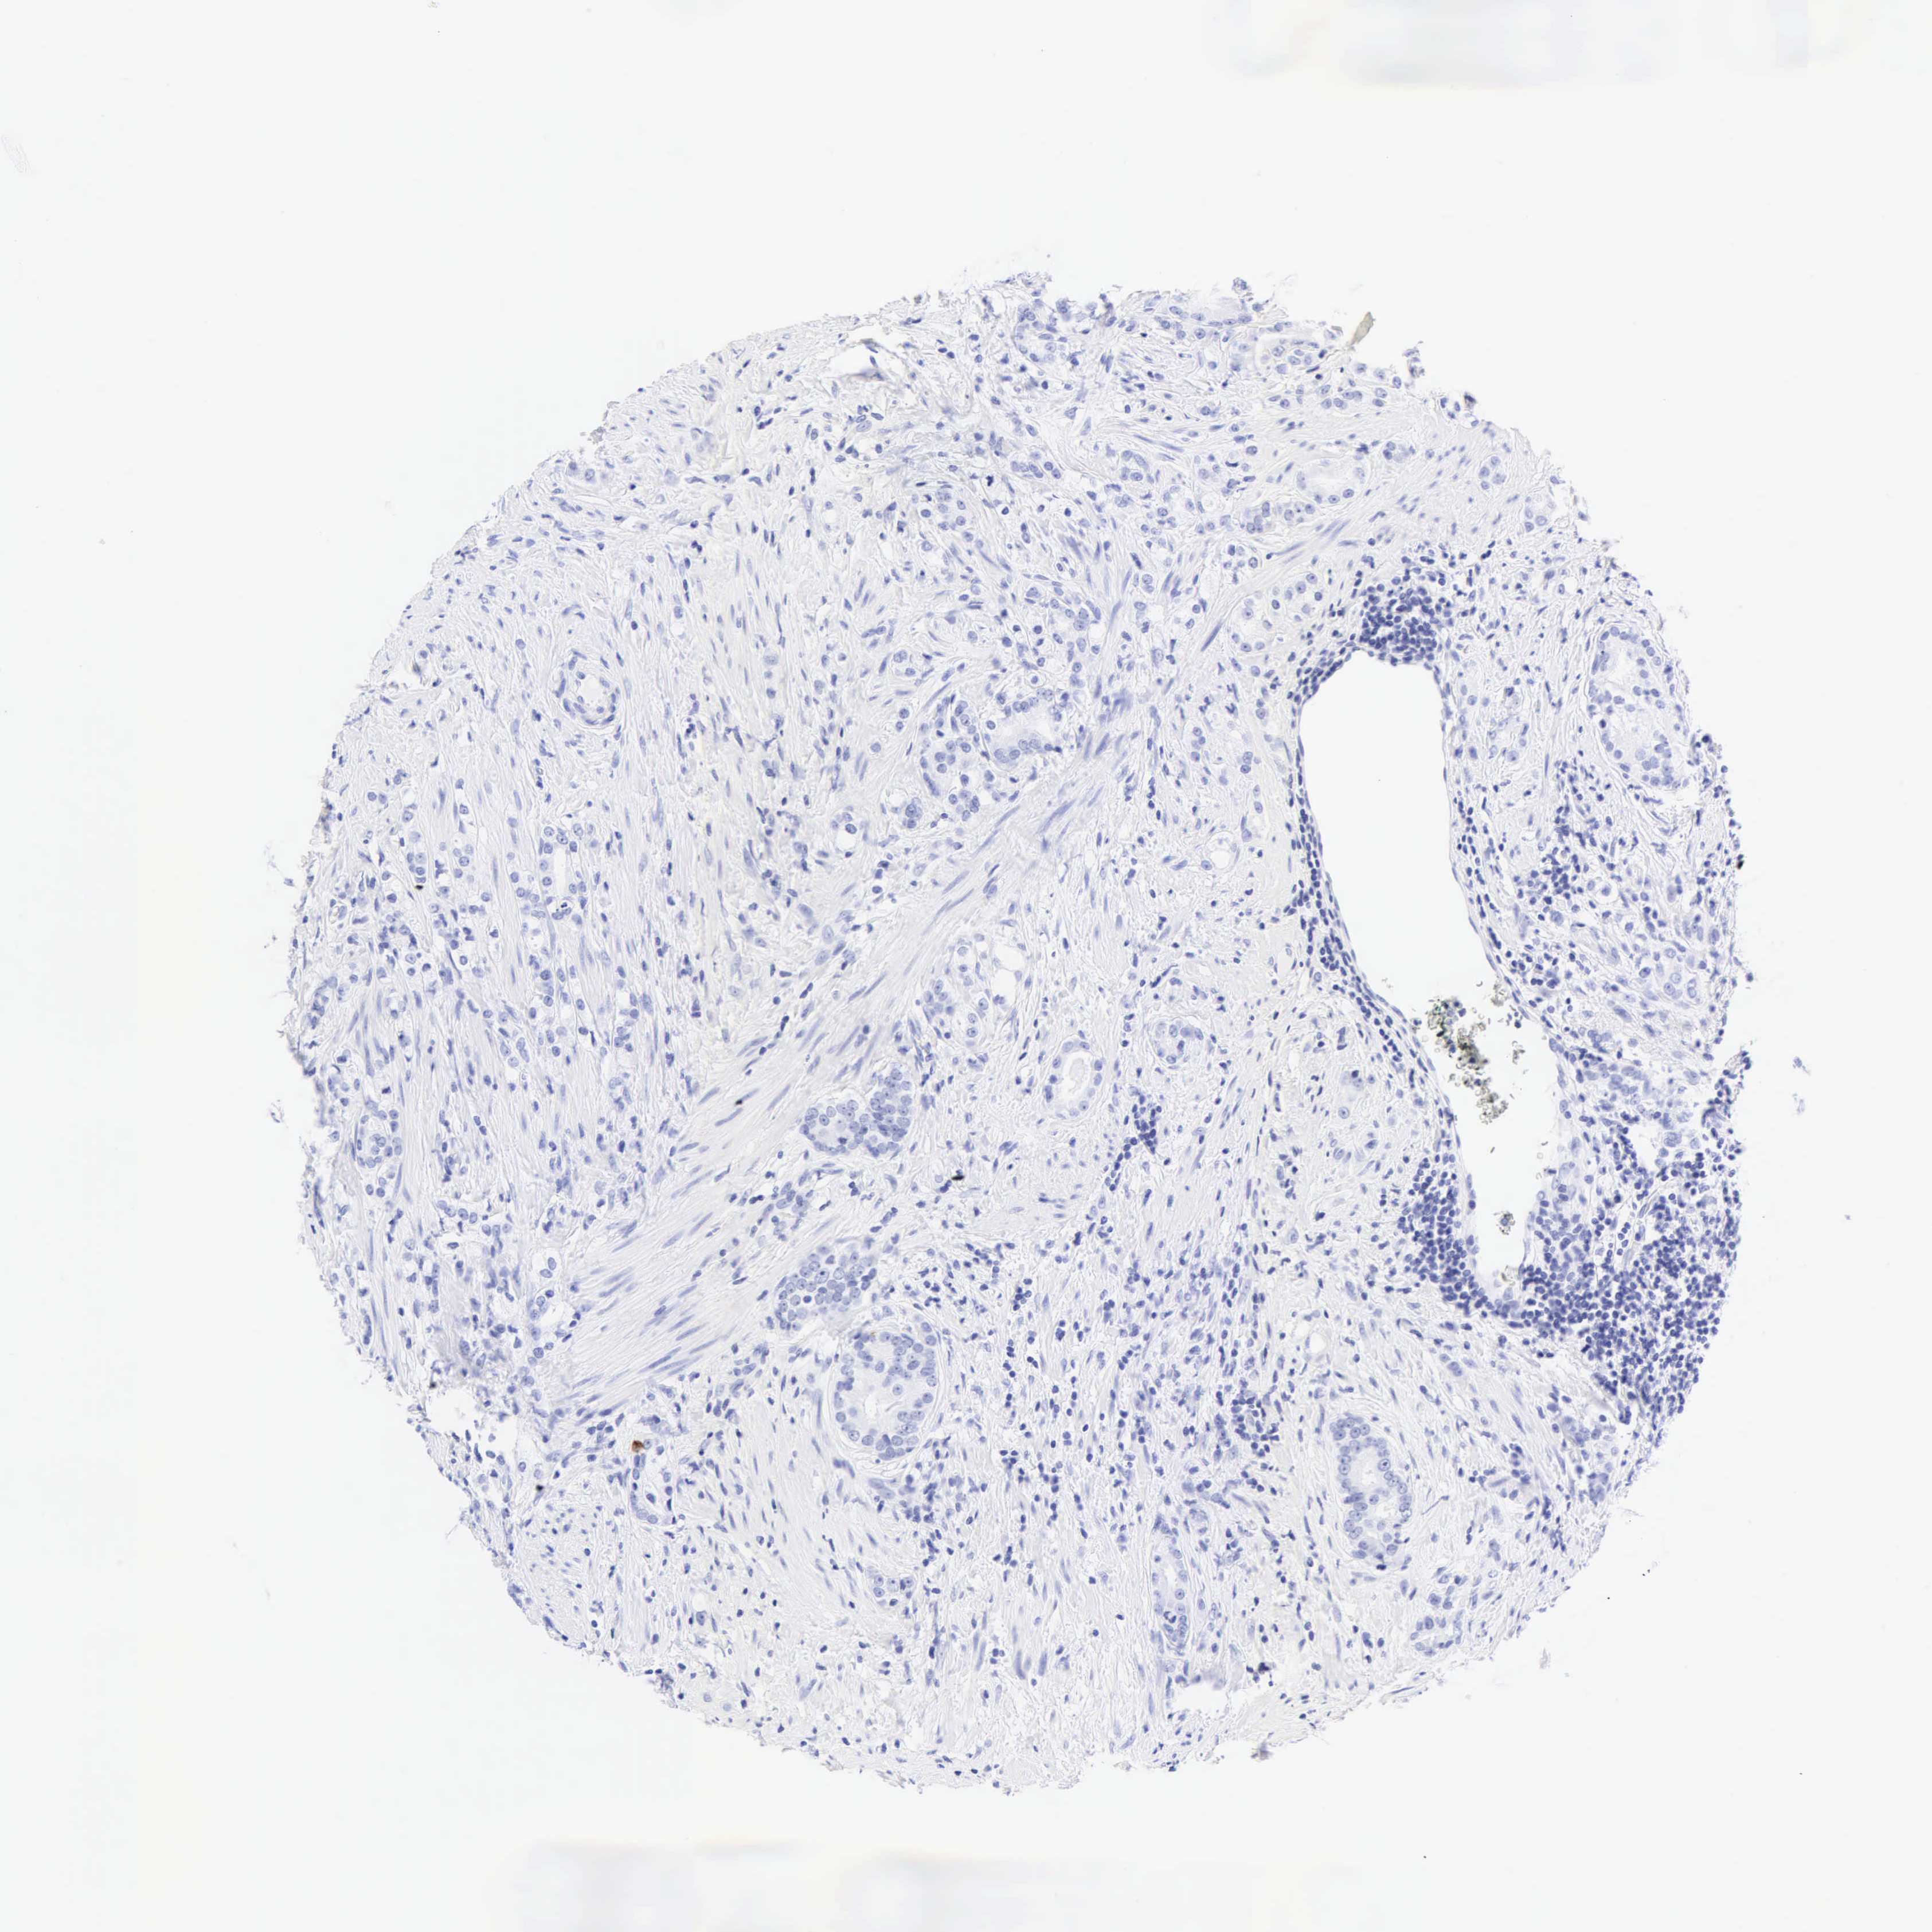

PROSTATE CANCER - Protein expressioni

A mouse-over function shows sample information and annotation data. Click on an image to view it in a full screen mode. Samples can be filtered based on level of antibody staining by selecting one or several of the following categories: high, medium, low and not detected. The assay and annotation is described here.

Note that samples used for immunohistochemistry by the Human Protein Atlas do not correspond to samples in the TCGA dataset.

Antibody stainingi

Antibody staining in the annotated cell types in the current human tissue is reported as not detected, low, medium, or high, based on conventional immunohistochemistry profiling in selected tissues. This score is based on the combination of the staining intensity and fraction of stained cells.

Each image is clickable and will lead to virtual microscopy that enables deeper exploration of all samples and also displays staining intensity scores, fraction scores and subcellular localization as well as patient and tissue information for each sample.

Antibody HPA024309

Antibody HPA024684

Antibody HPA027236

Antibody CAB000032

Adenocarcinoma, High grade

Adenocarcinoma, Low grade

Adenocarcinoma, Medium grade